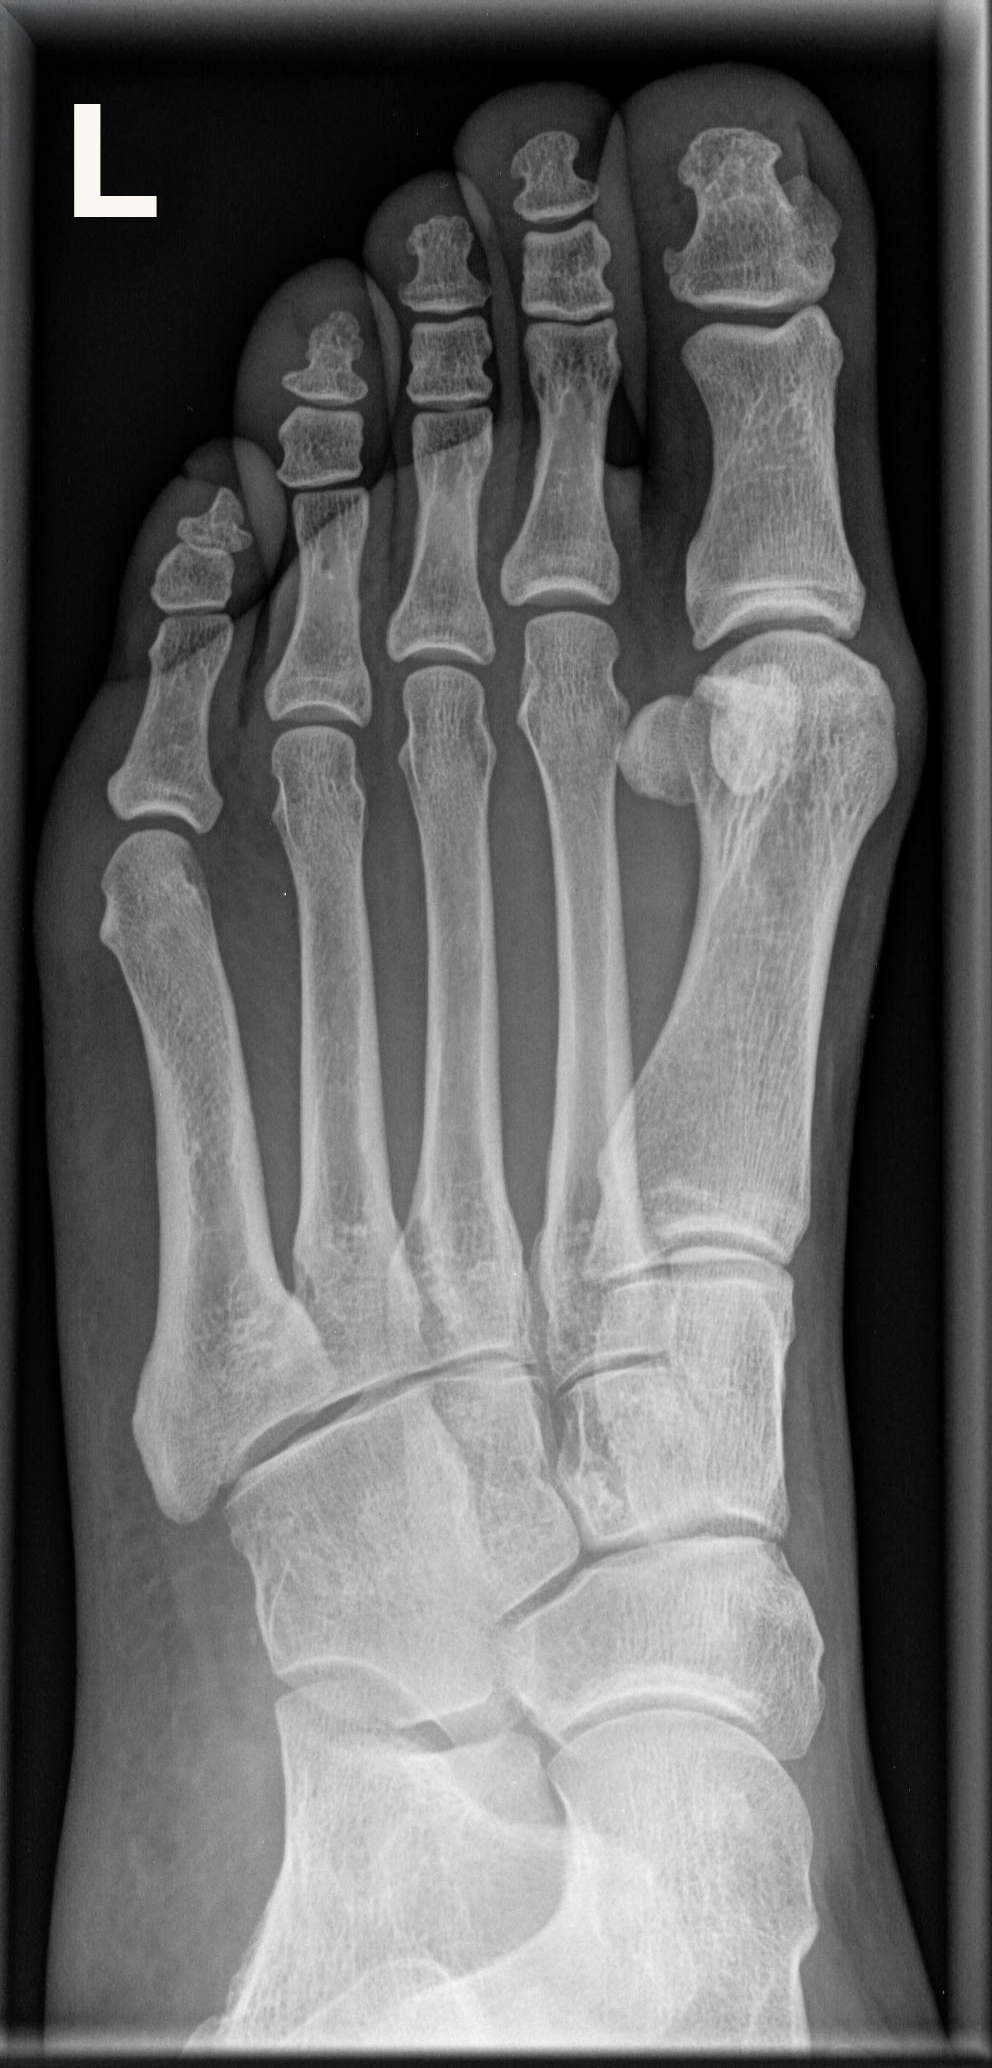

Fuß schräg (2. Ebene, chirurgisch)

Technik

• FDA: 1,05 m

• Ausgangsformat: 24/30

• Übertischaufnahme

Indikation

Fraktur

Lagerung

sitzend/ liegend auf Tisch

Knie gebeugt und Fuß aufgestellt

Basis Ossa metatarsalia 1-5 eine Höhe

(ca. 45° Kleinzehenseite angehoben)

Zentralstrahl

senkrecht auf Objektmitte

Einblendung

gesamter Fuß einschließlich Ferse

Qualitätskriterien

Freie Darstellung der Mittelfußknochen und Zehen sowie gute Beurteilbarkeit der Fußwurzelknochen, insbesondere des Lisfranc- und Chopartgelenks.